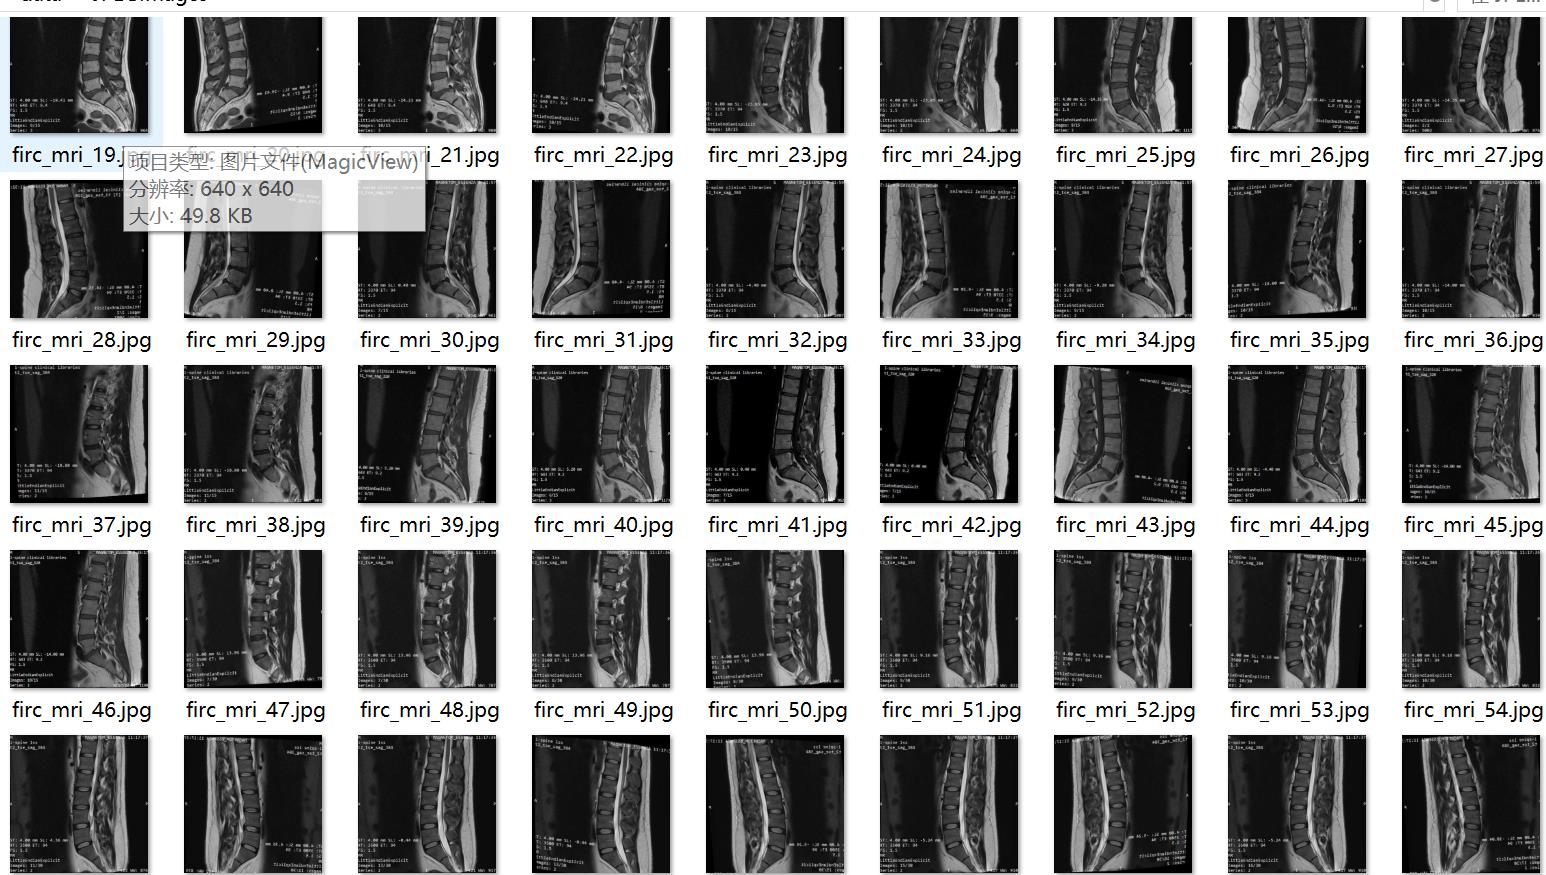

图片数量(jpg文件个数):666

图片分辨率:640x640